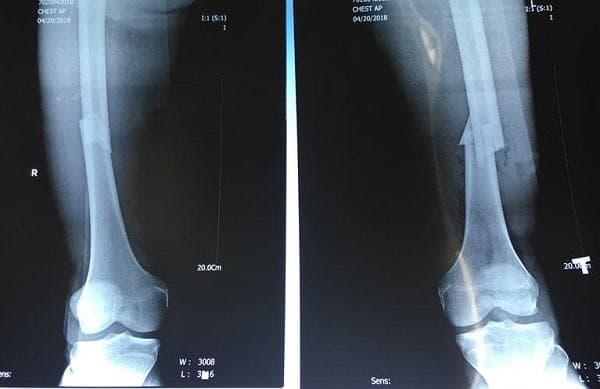

Gãy xương chày bao lâu thì lành? Phụ thuộc vào yếu tố nào?

Xương chày là một trong 2 xương lớn ở cẳng chân. Đây là xương rất quan trọng và có kích thước lớn. Tuy nhiên nếu gặp phải những chấn thương, tác động mạnh như té ngã, tai nạn… cũng có thể gây gãy xương chày. Vậy gãy xương chày bao lâu thì lành? Gãy xương […]